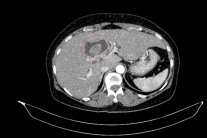

Phạm Vũ Hiệp nhớ lại thời điểm anh đối mặt với bệnh tật. Khi đó, mọi tương lai tốt đẹp đang rộng mở trước mắt, anh có một công việc ổn, những rạn nứt gia đình cũng phần nào được hàn gắn, rồi anh lấy vợ, xây dựng tổ ấm cho riêng mình. Con gái đầu lòng chào đời khiến niềm vui nhân lên gấp bội. Một lần, năm 2007, trong một chuyến công tác tại Singapore, anh bị đau bụng dữ dội và phải vào bệnh viện. Do không có thời gian khám kỹ lưỡng nên bác sĩ cho thuốc và khuyên khi về nước cần khám kỹ hơn. Về Việt Nam, những cơn đau hành hạ ngày một nhiều hơn, anh đi nhiều bệnh viện, trải qua nhiều xét nghiệm, chiếu chụp, siêu âm, nội soi… Mỗi lần khám như thế, anh đi tối thiểu 2 bệnh viện cho chắc chắn, nhưng tất cả đều kết luận là rối loạn tiêu hóa, viêm dạ dày… Nhưng cứ có thuốc thì đỡ đau, hết thuốc thì cơn đau lại hành hạ ngày một dữ dội thêm, cân nặng sụt giảm rất nhanh. Mãi đến khi anh tự sờ thấy khối u trong ổ bụng mình, anh quyết định ra Hà Nội khám lại và điều trị. Bác sĩ kết luận anh bị ung thư hạch mang tên lymphome-malin. Anh phải phẫu thuật cắt gần 1m ruột.